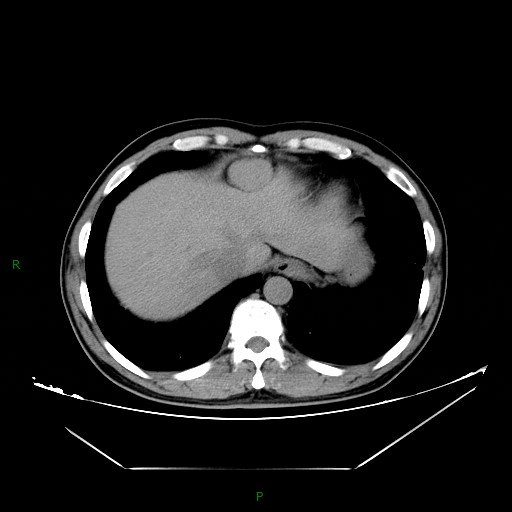

CT 平扫:

CT:形态大多表现为结节、团块状,密度均匀,边缘清楚,直径均<4 cm,病灶与被种植的脏器呈宽基底相连。平扫时病灶密度与正常肝脏或肌肉相仿,CT 值约为 40 HU-70 HU,增强后三期强化均匀,动脉期呈明显强化,门脉期呈持续性强化,延迟期强化稍减退,各期强化方式与脾脏实质一致。